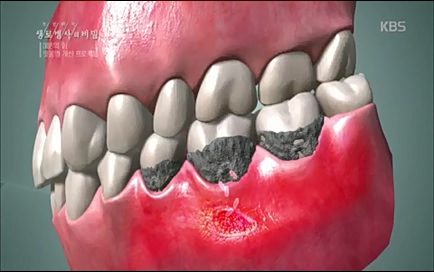

뿌리 끝까지 (잇몸)뼈가 굉장히 많이 녹아있고

지금 상당히 많이 관찰됩니다. 특히 앞니 아래쪽 부분에는 이런 치태들이 많이 생기는데